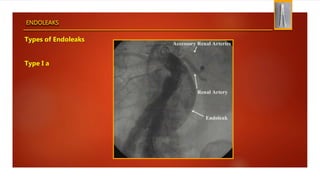

Types of Endoleaks

Type I a

ENDOLEAKS